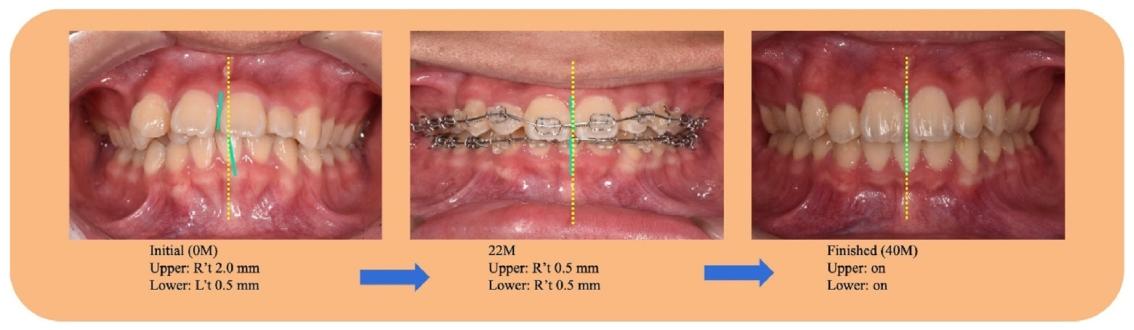

治疗前正面像可见面部不对称,口内照显示阻生牙、缺牙及反锁合

❶ 外观改善

✅ 侧面凸度减小,唇部自然闭合,面部对称性提升

✅ 前牙覆盖从6mm降至2mm,覆合正常化

治疗后面像对称,口内照显示整齐牙列与正常咬合